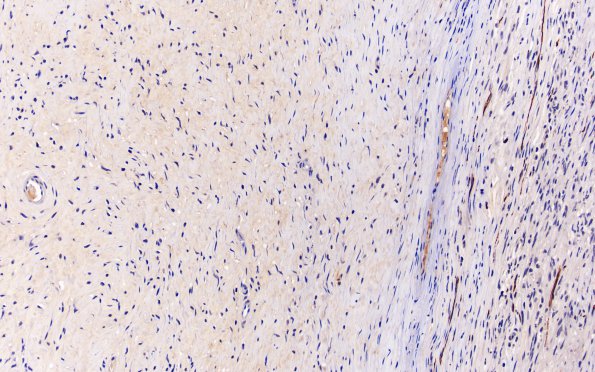

5E Schwannoma, cellular (Case 5) NF 20X 1

A MIB-1 immunostain demonstrates a very low proliferative index.